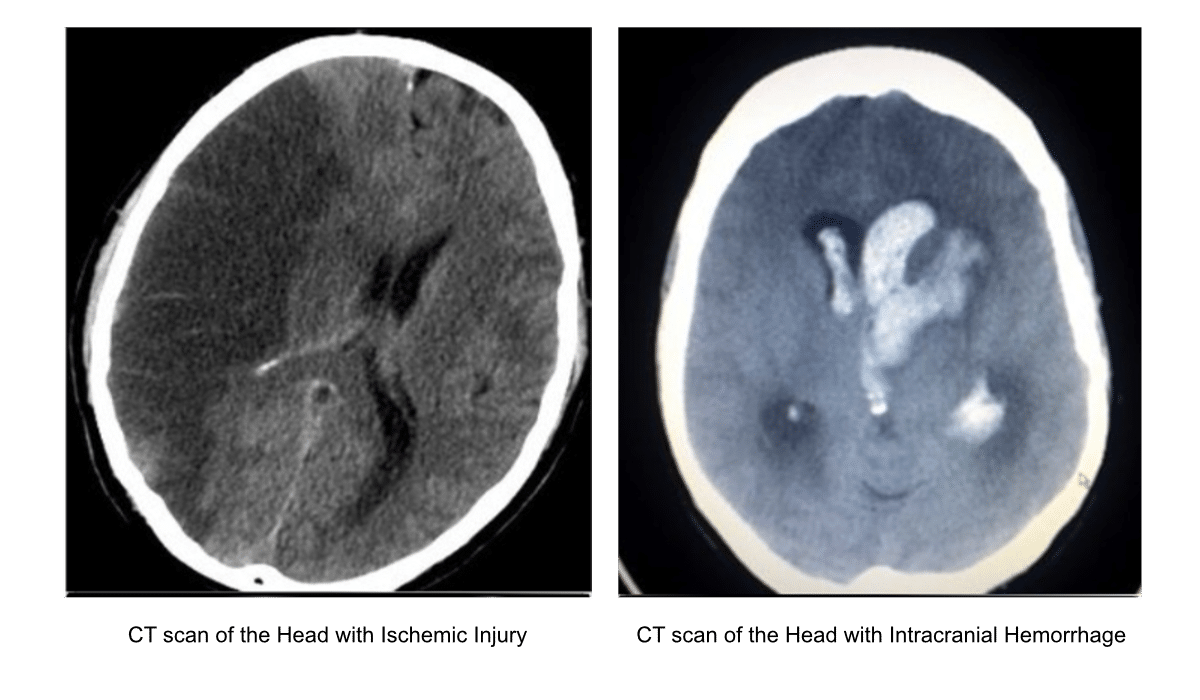

- The CT scan is the most important tool to distinguish between ischemic and hemorrhagic stroke.

CT Scan: Ischemic versus Hemorrhagic Stroke

A non-contrast CT scan is required to differentiate between an ischemic clot and a hemorrhagic bleed.

Because the therapies for a clot are fatal if given to a patient with a brain bleed, treatment cannot begin until providers perform a non-contrast CT scan of the head.3 This imaging determines whether the patient is experiencing an ischemic stroke (blockage) or a hemorrhagic stroke (bleeding from a ruptured vessel or aneurysm).

Crucial Rule: Providers must absolutely withhold all fibrinolytic and anticoagulation medications (like tPA, aspirin, or heparin) until the CT scan conclusively rules out a hemorrhagic stroke. If the institution lacks a CT scan machine, they must stabilize the patient and immediately transfer them to an equipped hospital.

Time is critical: CT scan images must be completed within 25 minutes of patient arrival in the ED, and an expert radiologist should interpret them within 45 minutes. While advanced imaging like CT perfusion, CT angiography, or brain MRI can provide deeper diagnostic insight, ordering them should never delay the administration of fibrinolytic treatments if the patient is already a candidate.

CT scan for ischemic stroke (left) and hemorrhagic stroke (right).